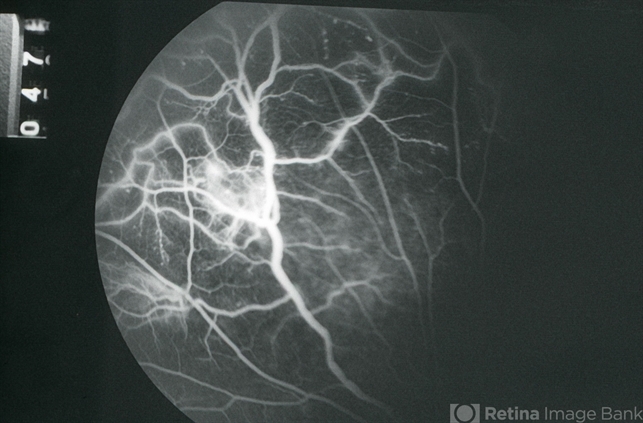

- EALES DISEASE

- Eales disease, neovascularization elsewhere (NVE), fluorescein angiogram (FA), FA mid phase

- Mid-phase fluorescein angiogram image of the left eye of a 23-year-old Vietnamese female with Eales Disease showing the retinal vascular abnormalities, capillary loss, and a focus of NVE; V.A.= 20/25-2.